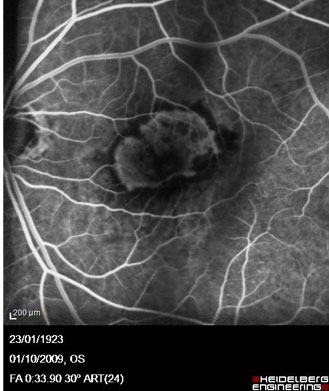

Angiographie Numérisée

L'Angiographie est un examen fondamental dans l'arbre décisionnel diagnostique des pathologies rétiniennes qui permet de visualiser les vaisseaux de la rétine à l'aide d'un colorant de contraste injecté par voie intraveineuse dans le bras.

L'angiographie peut être réalisée avec deux catégories de colorants, chacun possédant des spécificités :

- La Fluorescéine — colorant jaune, le plus couramment utilisé, qui met en évidence les petits vaisseaux irriguant la rétine

- Le Vert d'Indocyanine (ICG) — colorant vert utilisé pour visualiser le réseau vasculaire sous la rétine (choroïde)

Angiographie — Néovaisseaux (DMLA)